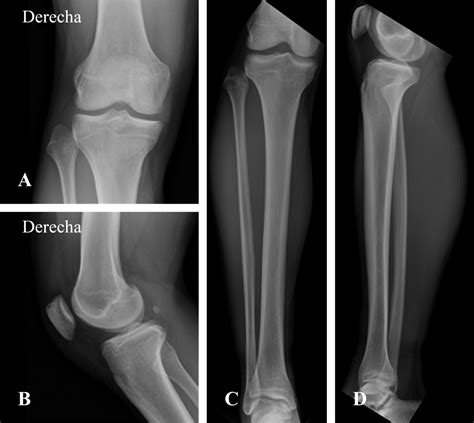

Diagnostic Approaches

Diagnosing subject within the superior tibiofibular joint normally affect a combination of physical palpation and provocative testing. A healthcare provider will typically do the followers:

• Imagination: While X-rays are often clear, MRI or echography can be used to project soft tissue inflammation or ligamentous tears surrounding the articulation.